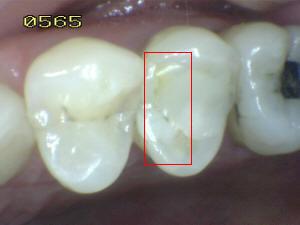

Sistema Internacional para la Detección y Evaluación de Caries (ICDAS)

¿Determine los códigos pertinentes a cada imagen?

Click en el hipervínculo: Para comparar el resultado de su diagnóstico